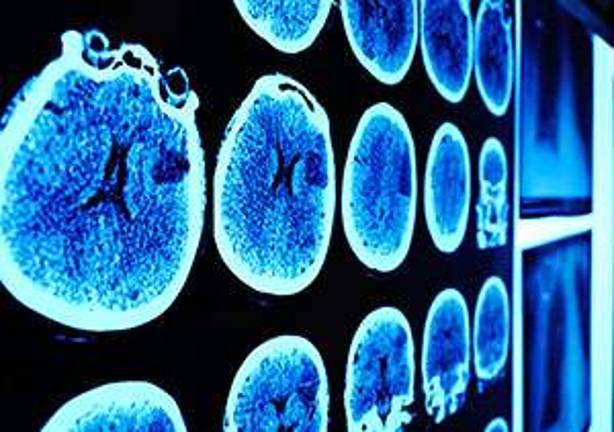

A large study for the first time has shown that people as young as their 40s have stiffening of the arteries that is associated with subtle structural damage to the brain that is implicated in cognitive decline and Alzheimer’s disease later in life.

The large study, led by the UC Davis School of Medicine, involved approximately 1,900 participants in the Framingham Heart Study, who underwent brain magnetic resonance imaging (MRI), as well as arterial tonometry.

The study found that, among young healthy adults, higher aortic “stiffness” was associated with reduced white matter volume and decreased integrity of the gray matter, and in ages much younger than previously described.

The tests measured the force of arterial blood flow, the carotid femoral pulse wave velocity or CFPWV — the reference standard for noninvasive measurement of aortic stiffness — and its association with subtle injury to the brain’s white and gray matter. The research found that increased CFPWV was associated with greater injury to the brain.